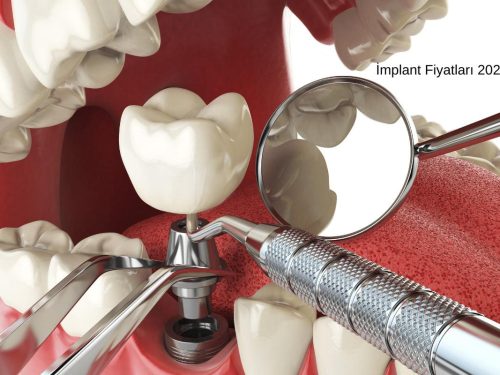

İmplant Tedavisi Ne Kadar Sürer?

Eğer ki Hastanın kemik yapısı uygun ise İmplant uygulaması aynı gün içerisinde yapılabilir.

İmplant Fiyatı Nedir?

İmplant Fiyatları için hemen bizimle iletişime geçebilirsiniz. İmplant Fiyatları 300 Euro'dan başlamaktadır.